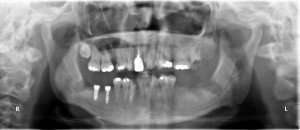

術後のパノラマです。2本のインプラントの埋入ポジションは理想的です。

右下6番部位にφ3.3mm×11mmと7番部位にφ4.1mm×9mmをそれぞれ埋入しました。

6番部位は、厚みが少なくて頬側に裂開を生じましたので、3.3mm径のインプラントを使用し、歯槽頂からボーンチップを採取して補填しました。

パラレルピンを使用して平行性を確認、近心のインプラントがやや遠心傾斜していましたので、次のドリリングで修正しました。